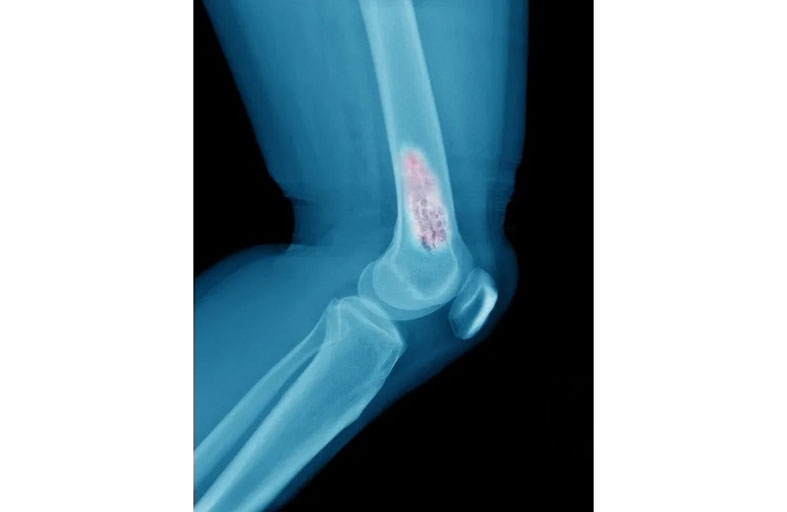

خمسة أعراض يتم تشخيصها بشكل خاطئ قد تشير إلى الإصابة بسرطان العظام

ويمكن أن يبدأ سرطان العظام في أي عظم في الجسم، لكنه يؤثر بشكل شائع على الحوض أو العظام الطويلة في الذراعين والساقين.

وغالبا ما يطلق على سرطان العظام الأولي بالساركوما (Sarcoma)، وهناك عدة أنواع مختلفة من الساركوما، وكل واحدة تُميز طبقة عظام مختلفة، وأكثرها شيوعا هي الساركوما العظمية (Osteosarcoma)، وساركوما إيوينغ (Ewing)، والساركوما الغضروفية (Chondrosarcoma)، والورم الحبلي (Chordoma) وهو شكل نادر غالبا ما يتم تشخيصه عند البالغين.